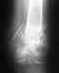

Здравствуйте. У меня оскольчатый винтообразный перелом голени. Сделано вытяжение, поставлен апп.Илизарова. Через 1,5 мес. на снимке трещина, сделана подтяжка спицы, снимок назначен через месяц.Если сопоставление полностью не произошло, возможно ли его будет исправить через месяц?Заранее, спасибо.